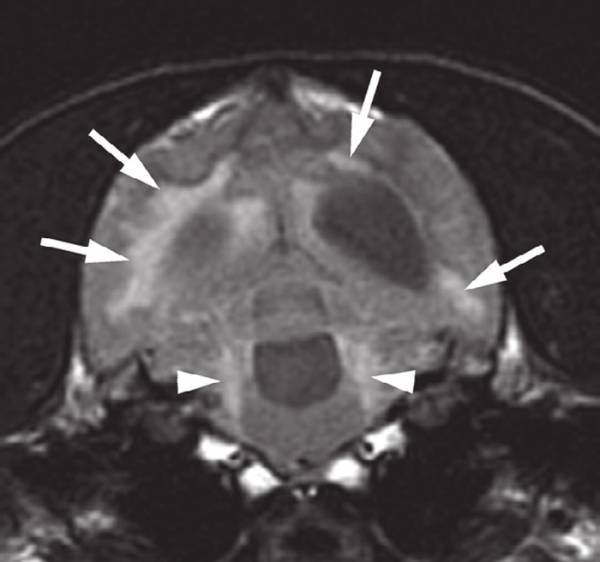

Инфекционный перитонит начинается с ухудшения самочувствия кота, снижения аппетита, иногда – рвоты. Постепенно животное теряет вес, слизистые оболочки становятся бледнее. Влажная форма перитонита сопровождается развитием асцита (скопление жидкости в брюшной полости), поражением кровеносных сосудов, нарушением печени и почек. Мышцы теряют эластичность, возникают судороги, поражается ЦНС.

Коронавирусный перитонит может иметь и так называемую сухую форму, при которой во внутренних органах появляются гранулемные образования. Тяжесть такого заболевания зависит от того, на каких органах сформировались «узелки» и насколько сильно они поразили ткани. Сухая форма перитонита проявляется значительным снижением веса, а на более поздних стадиях – нарушением функций внутренних органов, иногда нервной системы и глаз. В организме могут присутствовать сразу две формы заболевания, или одна может перейти в другую.